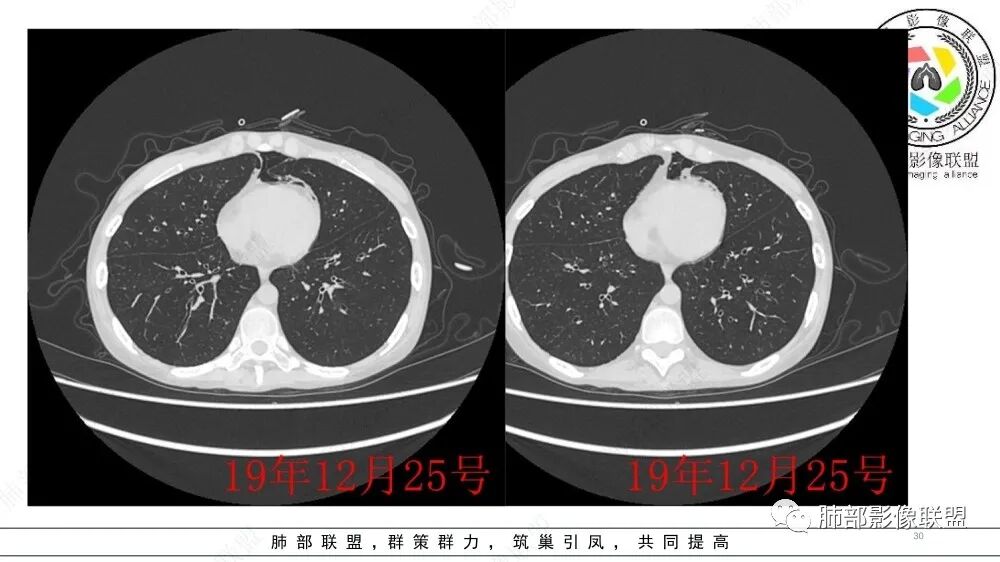

干细胞移植后,肺CT较前比较两肺支气管轻度扩张,管壁增厚,两肺透亮度增高,纵膈气肿,考虑闭塞性细支气管炎

这个主要是临床,影像比较单一,有纵隔气肿;两侧对比:后者确实肺密度减低,体积增大,有气体潴留的特点

干细胞移植后,支气管轻度扩张,纵隔气肿,符合干细胞移植后BO,胸腔漏气综合征